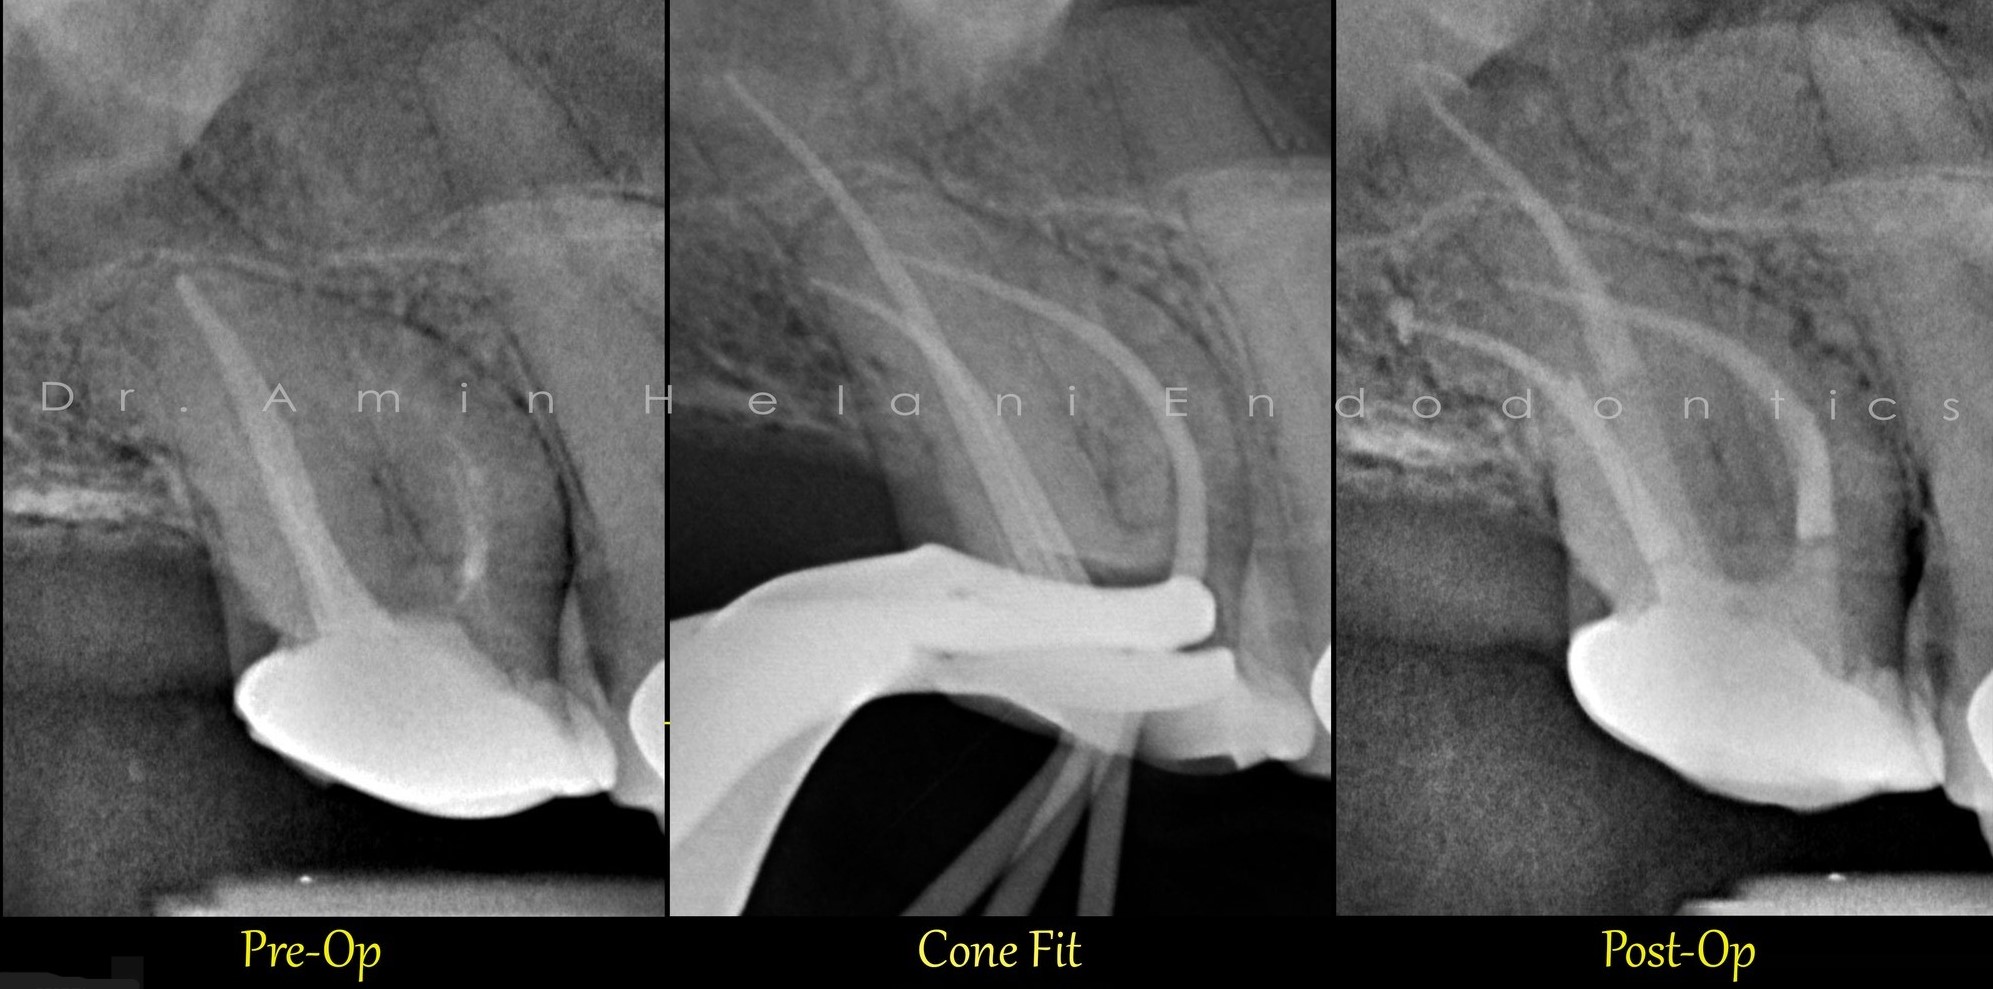

Gekrümmter Kanal im unteren Molaren